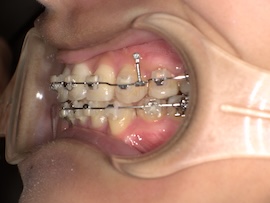

さらに1ヶ月後、

左上の7番目を抜歯してから約9ヶ月が経過しましたが、代わりに活かしていきたい親知らずが出てこないのでついに牽引(歯茎を切って引っ張り出す)をすることになりました。

内側の装置が新しくなるので今回は型取りをして準備を進めていきます。

右上の6番目にバンド(金属の輪っか)を装着するためブラケットは一時的に外しています。

左上の奥に打っていた矯正用アンカースクリューですが、今回も安定せず揺れてきてしまったので抜くことになりました。

ある程度噛み合わせは良くなってきたのであとはゴムかけだけでも問題ないとのことです。